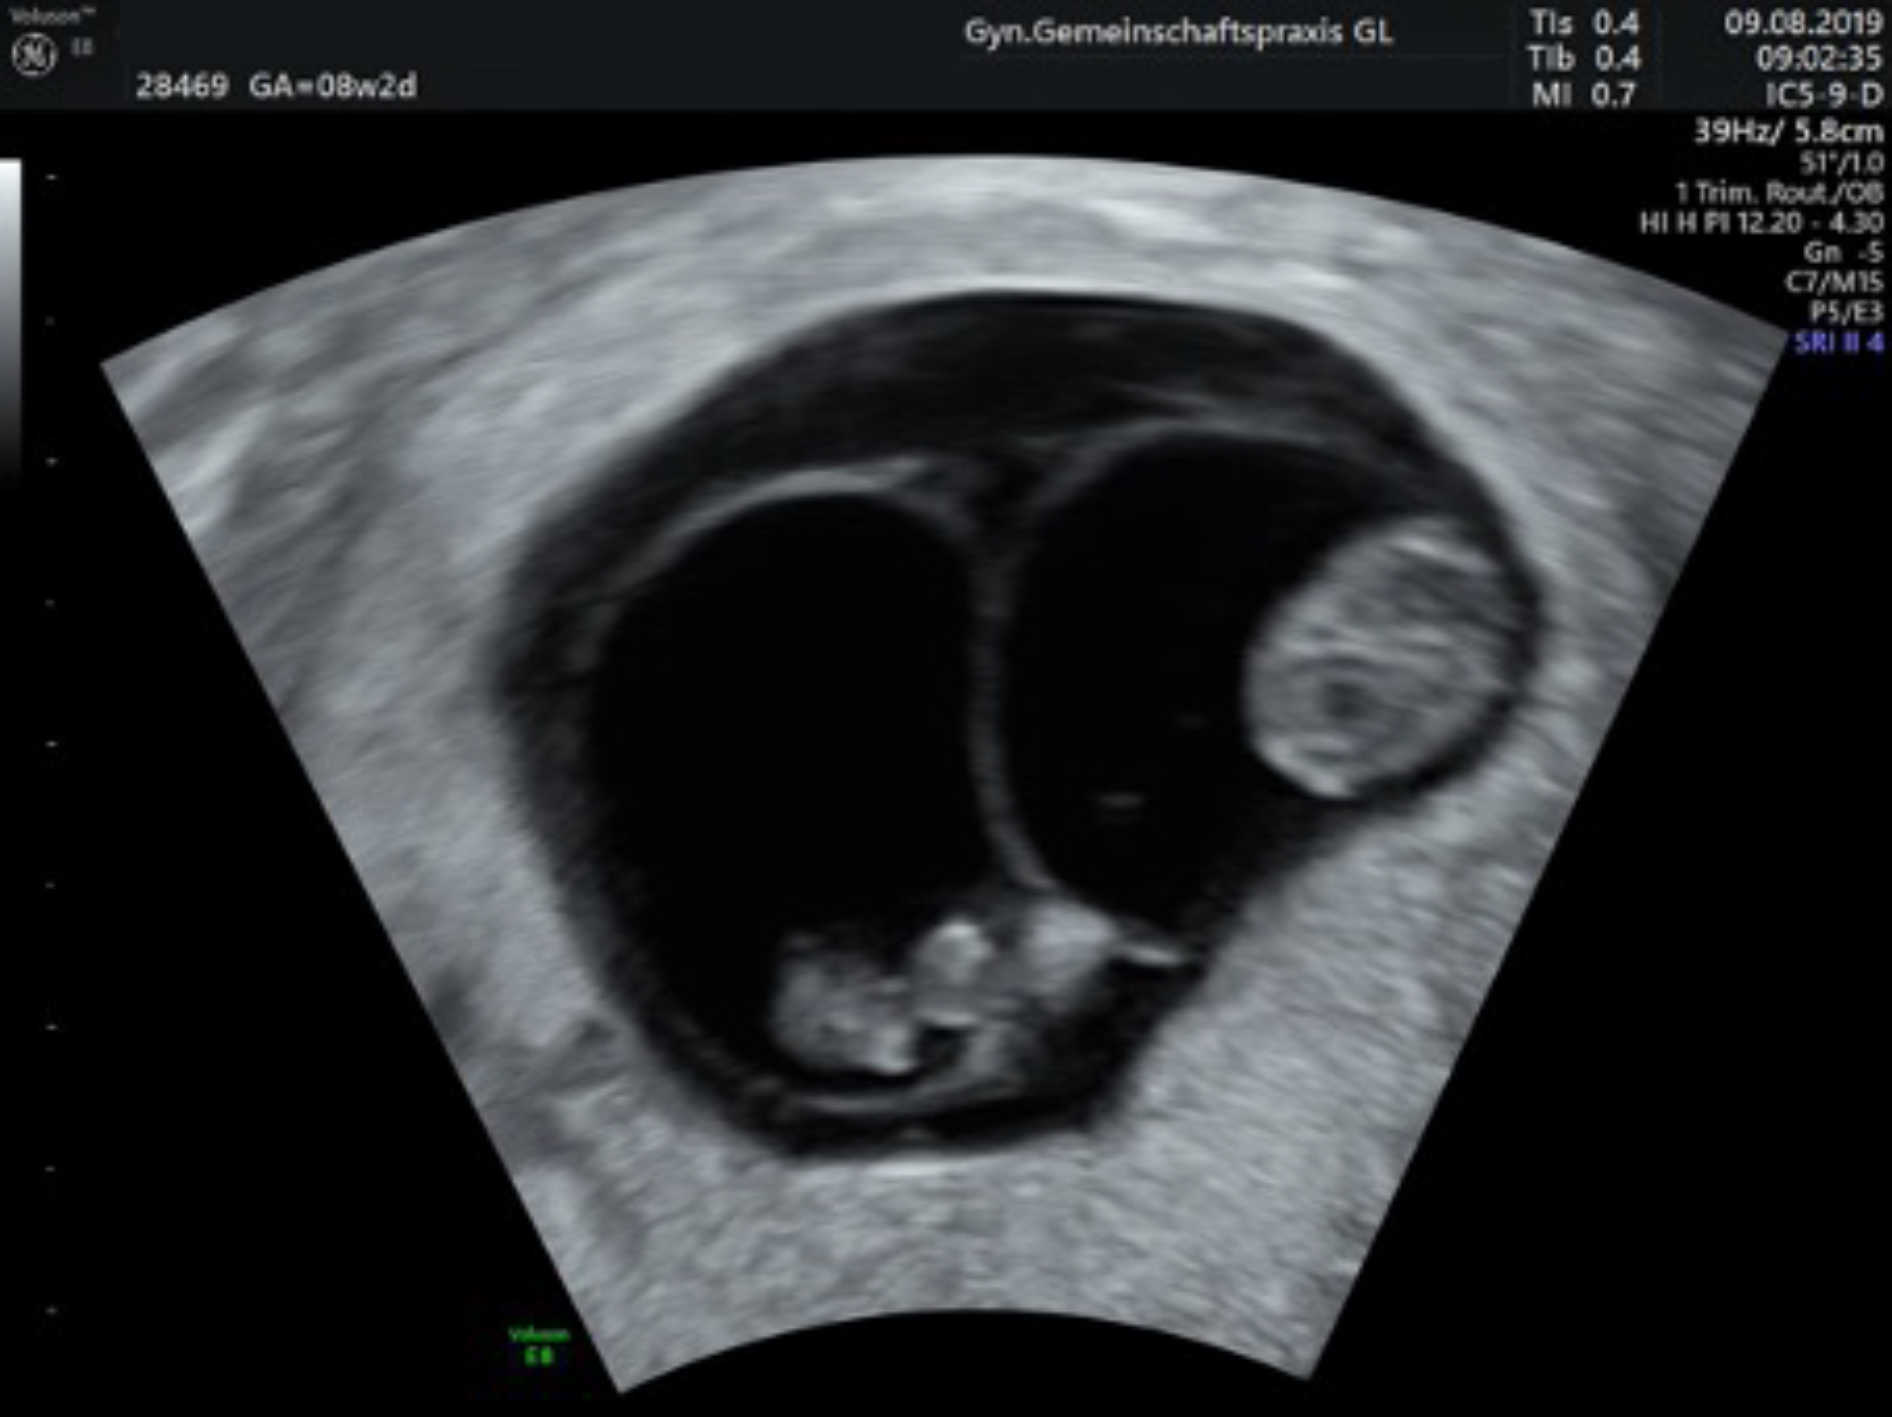

Die gesetzliche Krankenkasse sieht drei Ultraschalluntersuchungen im Laufe einer unauffälligen Schwangerschaft vor: 9. – 12. SSW, 20. – 22. SSW und 29. – 32. SSW.

Ersttrimesterscreening mit individueller Risikoberechnung

(auch Nackentransparenzmessung/frühe Organdiagnostik genannt)

Zwischen der 12. und 14. Schwangerschaftswoche lagern die Kinder Flüssigkeit im Bereich des Nackens ein. Bei manchen Kindern ist dies verstärkt der Fall und kann dann zusammen mit Veränderungen bestimmter Blutwerte der Mutter einen Hinweis auf eine Chormosomenstörung (z. B. ein Down-Syndrom) geben.